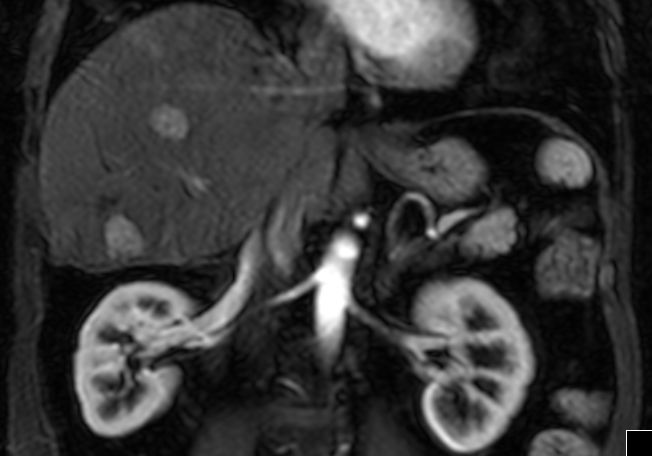

| Fall 2 | 58-jährige Frau mit Adnektektomie beiderseits vor vielen Jahren. Jetzt Peritonealkarzinose mit Verkalkungen. CA 12-5 = 1100, CA 15-3 = 41. Histologie: Proliferate und Infiltraten eines papillär strukturierten Karzinoms. Vergrößerte hyperchromatische Zellkerne. Die mitotische Aktivität ist etwas erhöht. Darstellung von Psammomkörpern. Tumorzellen positiv mit BerEP4, CK 7, WT1 und Östrogenmarker. Kein Nachweis von Calretinin und CK. | |||